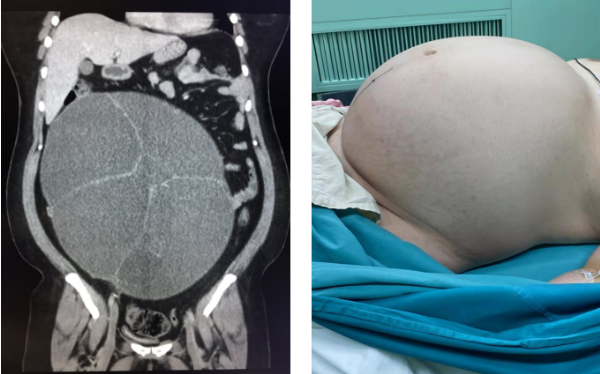

2019年12月23日,早上剛一上班,就收入一位胖胖的患者。她穿著大羽絨服罵罵咧咧走進(jìn)病房,認(rèn)為父母非親生,典型的精神分裂癥。不想,脫下衣服時,卻著實嚇到了我?;颊吒共慨惓E蚵?,摸上去十分堅硬,就像懷了足月的雙胞胎,快要撐破了一樣,坐在椅子上還得用手托著這個“大球”,喘氣也有些困難?!霸趺丛袐D也收上來了!”我心里的第一反應(yīng)。詢問下,患者自稱懷孕了。我正得意自己料事如神,卻被家屬告知,近一年來患者肚子越長越大,她總說懷孕了,卻又毫無理由拒絕去醫(yī)院檢查。她長期不出門,從未交往男友,絕無懷孕可能。聽到這個答案,我自嘲居然這么輕易就被患者的妄想騙到了。心里的石頭剛要放下,轉(zhuǎn)瞬又覺得壓力襲來。既然不是懷孕,那這里面一定另有“名堂”。是什么病,有沒有風(fēng)險,該怎么護(hù)理,如何治療……一連串的問題涌進(jìn)我的腦中。

我的上級醫(yī)生趙燕老師了解情況后果斷安排了腹部CT,結(jié)果顯示腹部巨大囊性占位(卵巢來源)伴腹疝形成。按常規(guī),這么嚴(yán)重的軀體病比精神病更“要命”,得先去看軀體病。這個建議當(dāng)即被家屬拒絕。老兩口表示患者對他們非打即罵,根本不能配合,他們都已年逾古稀,走路都顫顫巍巍,如果能去早就去了,即便現(xiàn)在承擔(dān)一切后果也實在是無法轉(zhuǎn)院。

家屬萬分感謝,激動地告知我們腫瘤是良性的,抽出15000ml囊液,體重減了17公斤。我們也如釋重負(fù),既為手術(shù)順利欣慰,也為患者身體康復(fù)開心。老人說,他們從沒遇到過這么好的醫(yī)院,這么負(fù)責(zé)任的醫(yī)生!老人拿著紅包感謝房主任在他們最困難的時候給予的莫大幫助,也被主任婉言謝絕。幫助患者、得到家屬的尊重和認(rèn)可,就是醫(yī)生的最大價值!